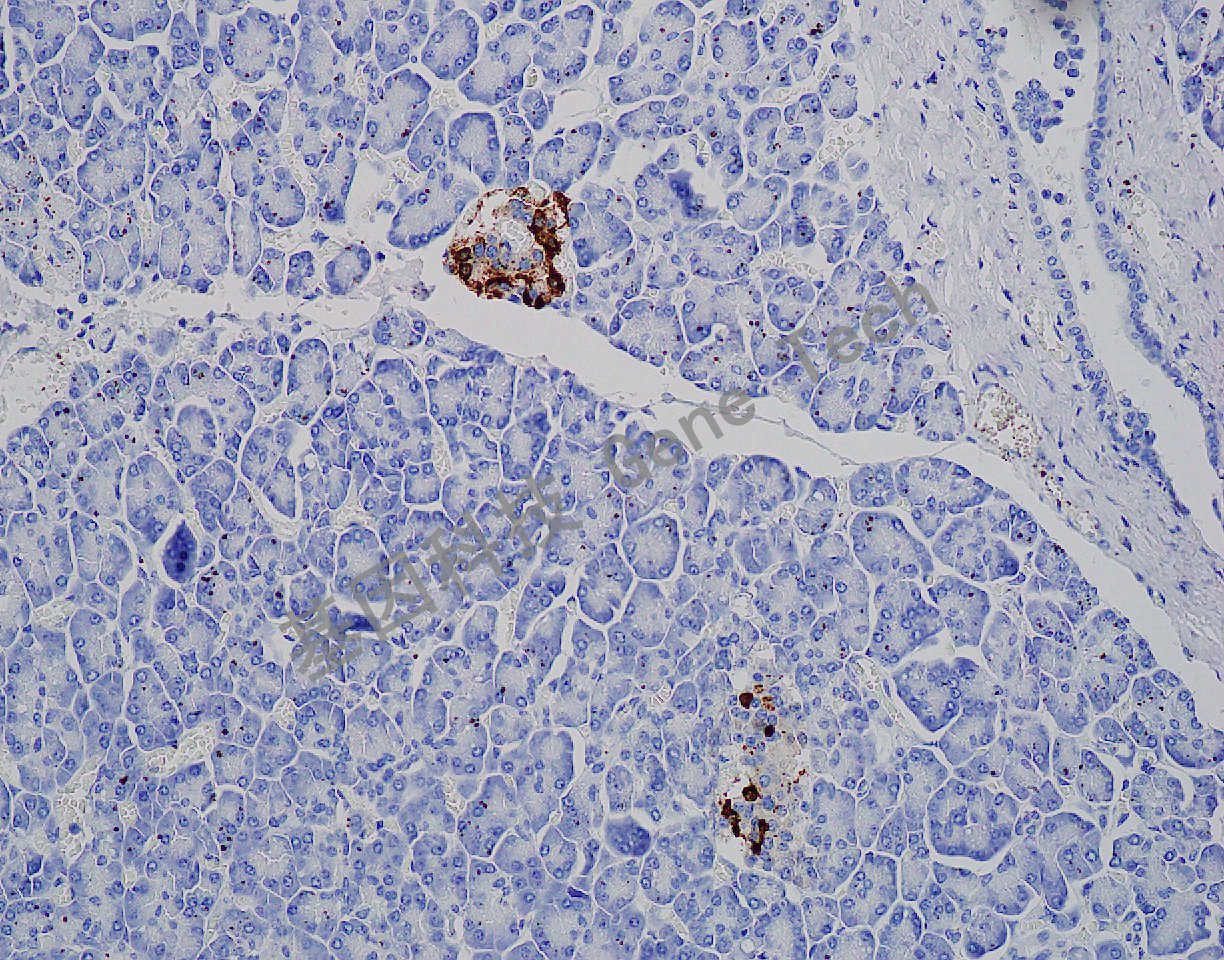

| 預處理:高pH熱修復 | 陽性部位:細胞漿 | 陽性對照:胰腺 |

| 胰腺石蠟切片,用 Somatostatin(GA0566)染色,細胞漿陽性,DAB 顯色。 | ||